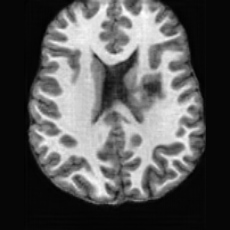

Pathology-to-Healthy Editing. Fig. 5 (a) presents comparison results on four input brain images with lesions of varying sizes, shapes, and densities. All competing models, although specialized for healthy brain image synthesis, struggle to reconstruct pathological regions, especially near lesion boundaries. In contrast, USB accurately reconstructs the corresponding healthy brain, even in challenging cases with large, high-density lesions where normal brain structures are almost completely obscured (last row). Tab. 2 provides a quantitative comparison for pathology-to-healthy editing, where USB achieves the best performance across all three datasets, demonstrating the effectiveness of its unified framework in reconstructing healthy brains from pathological inputs. Additional results are in Suppl. B.

Healthy-to-Pathology Editing. As shown in Fig. 5 (b), given a healthy brain image paired with a random lesion mask, USB seamlessly embeds the lesion into the healthy anatomy, producing realistic pathological appearances consistent with surrounding structural context. Yet UNA’s syntheses are visually unrealistic, with the conditioned lesion mask simply overlaid as a parallel layer onto the healthy brain. Tab. 3 further demonstrates USB’s superior performance. The evaluation was conducted on 100 pairs of lesion masks and healthy brains, with real stroke images

(a)PathologicalInput ImageSynthSR [18]Brain-ID [28]UNA [30]USBHealthyGround TruthRefer to captionRefer to captionRefer to captionRefer to captionRefer to captionRefer to captionRefer to captionRefer to captionRefer to captionRefer to captionRefer to captionRefer to captionRefer to captionRefer to captionRefer to captionRefer to captionRefer to captionRefer to captionRefer to captionRefer to captionRefer to captionRefer to captionRefer to captionRefer to caption(b)HealthyInput ImageConditionalLesion MaskUNA [30]USBRefer to captionRefer to captionRefer to captionRefer to captionRefer to captionRefer to captionRefer to captionRefer to captionRefer to captionRefer to captionRefer to captionRefer to captionRefer to captionRefer to captionRefer to captionRefer to caption

Figure 5: Comparison of bidirectional brain editing. (a) pathology-to-healthy, the circles and arrows highlight lesion regions and unsuccessful reconstructions; (b) healthy-to-pathology. Note that SynthSR and Brain-ID cannot perform healthy-to-pathology editing.